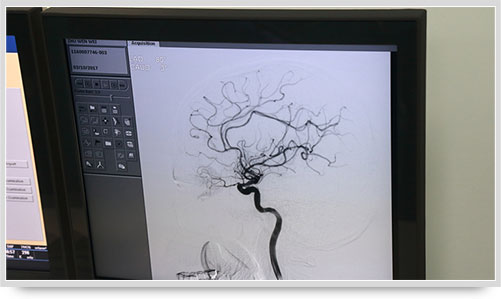

全腦血管造影術(shù)(DSA)是運用數(shù)字減影技術(shù)下進(jìn)行的全腦血管攝片,因此又稱數(shù)字減影血管造影。技術(shù)上一般采用局部麻醉,右側(cè)股動脈穿刺、置管,再將一根造影管通過腹主動脈、主動脈弓,選擇性進(jìn)入左右頸內(nèi)動脈和椎動脈后,分別造影,發(fā)現(xiàn)病灶后還應(yīng)行三維血管造影。造影圖像較以往所用的常規(guī)腦血管造影所顯示的圖像,更清晰和直觀,一些精細(xì)的血管結(jié)構(gòu)亦能顯示出來,是目前國際上公認(rèn)的血管性疾病診斷的“金標(biāo)準(zhǔn)”。

弓上造影、超選到頸內(nèi)動脈、椎動脈......在數(shù)字減影技術(shù)下,注入顯影劑后,導(dǎo)管經(jīng)患者右側(cè)股動脈在體內(nèi)推進(jìn),由于股動脈離腦血管距離較遠(yuǎn),中間“路程復(fù)雜”,對施術(shù)醫(yī)生的要求非常之高。

同時,手術(shù)臺前的液晶顯示儀屏幕上清晰地現(xiàn)顯出導(dǎo)管的路徑,在李主任的操作下準(zhǔn)確到達(dá)指定檢查部位,各條血管的“廬山真面目”清晰可見。